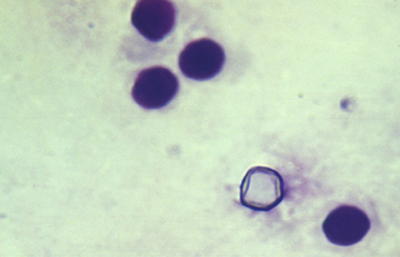

Coloración de Giemsa

En un frasco de Copli colocar 10 ml de la solución del colorante de Giemsa con 90 ml de un buffer fosfato 1/15 M y pH 6.8. Colorear el extendido fijado por 20 minutos. Lavar en agua corriente y dejar secar al aire. Aclarar en xileno por 5 minutos y montar con un medio de resina.

Los quistes Acanthamoebas midien de 10 a 16 µm de diametro, con capsula de forma circular o poligonal, a veces con angulaciones y ondulaciones, (Figura 41) teñido densamente azul oscuro. Membrana plasmática con tinción más tenue, concéntica, o retraida o colapsada asimétricamente. Coloración variable del citoplasma. (Figura 42, 43, 44 y 45)

Fig. 41 Giemsa. Original x400

Fig. 42 Giemsa. Original x200

Fig. 43 Giemsa. Original x160

Fig. 44 Giemsa. Original x160

Fig. 45 Giemsa. Original x200

Fig. 46 Giemsa. Original x160

En ocasiones cariosoma central prominente (en ojo de buey) (Figura 46) y quistes claros, vacios, compuestos sólo por la doble pared del quiste y membrana plasmática.

Cuando los quistes se localizan en el epitelio o en detritus colágenos y fibrinoides, el ectoquiste puede ser refringente, transparente o tenuemente azulado y el tendoquiste densamente coloreado de azul por el Giemsa. (Figura 47)

Los trofozoitos son más difíciles de visualizar, siendo mayores que los quistes. En preparaciones fijadas, son de forma circular, con pequeño núcleo y citoplasma con numerosos organelos y vacuolas (Figura 48)